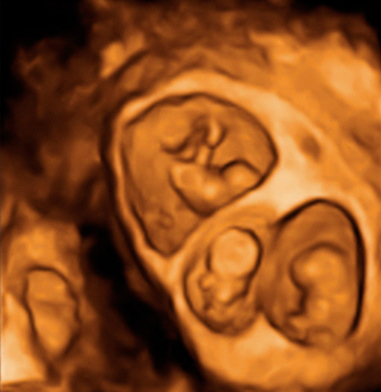

Ecografía semana 11: Bebé moviéndose en el útero

El bienestar fetal de este bebé de 11 semanas de gestación parece evidente a juzgar por su movimiento de brazos y piernas. Esta ecografía 4D ofrece el "baile" de este pequeñín, que está finalizando su primer trimestre de embarazo.

Ecografía en 4D de feto de 11 semanas moviéndose

Feto de 11 semanas de gestación con brazos y piernas en movimiento continuo dentro del útero materno. No se aprecian las extremidades con nitidez debido al "corte" de imagen que selecciona el ecografista.